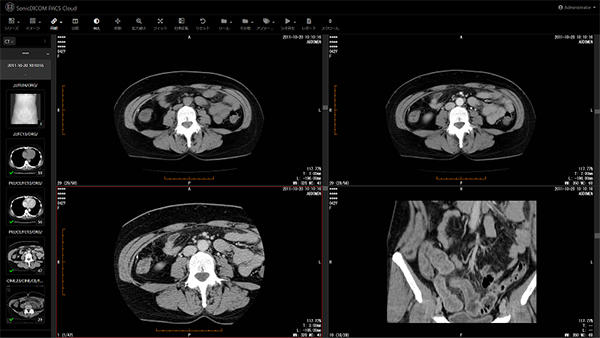

(株)ジウンは,2020年3月25日,医療機関や研究機関等に対して,医用画像を共有できるクラウド型医療画像管理システム『SonicDICOM PACS Cloud β』の無償利用枠を拡充した。これまで保存容量3GBまで無償提供していたが,今回の世界的な新型コロナウイルス(COVID-19)の感染拡大を受けて,医療機関や研究機関等の円滑な情報共有を支援するため,保存容量100GBまでを無償提供する。

本サービスは,CTやMRIなどの検査装置で撮影した医用画像をクラウド上で管理し,インターネットに接続できるパソコンやタブレット端末があれば,場所を選ばず画像を参照することができるサービス。専用ビューアのインストールが不要で,Webブラウザ(Google Chrome,Mozilla Firefox,Microsoft Edge等)から簡単に医用画像を参照することができる。またビューアは10ヵ国語に対応しており,データの保管先も世界6ヵ国7リージョンからユーザー自身で選択することができる。